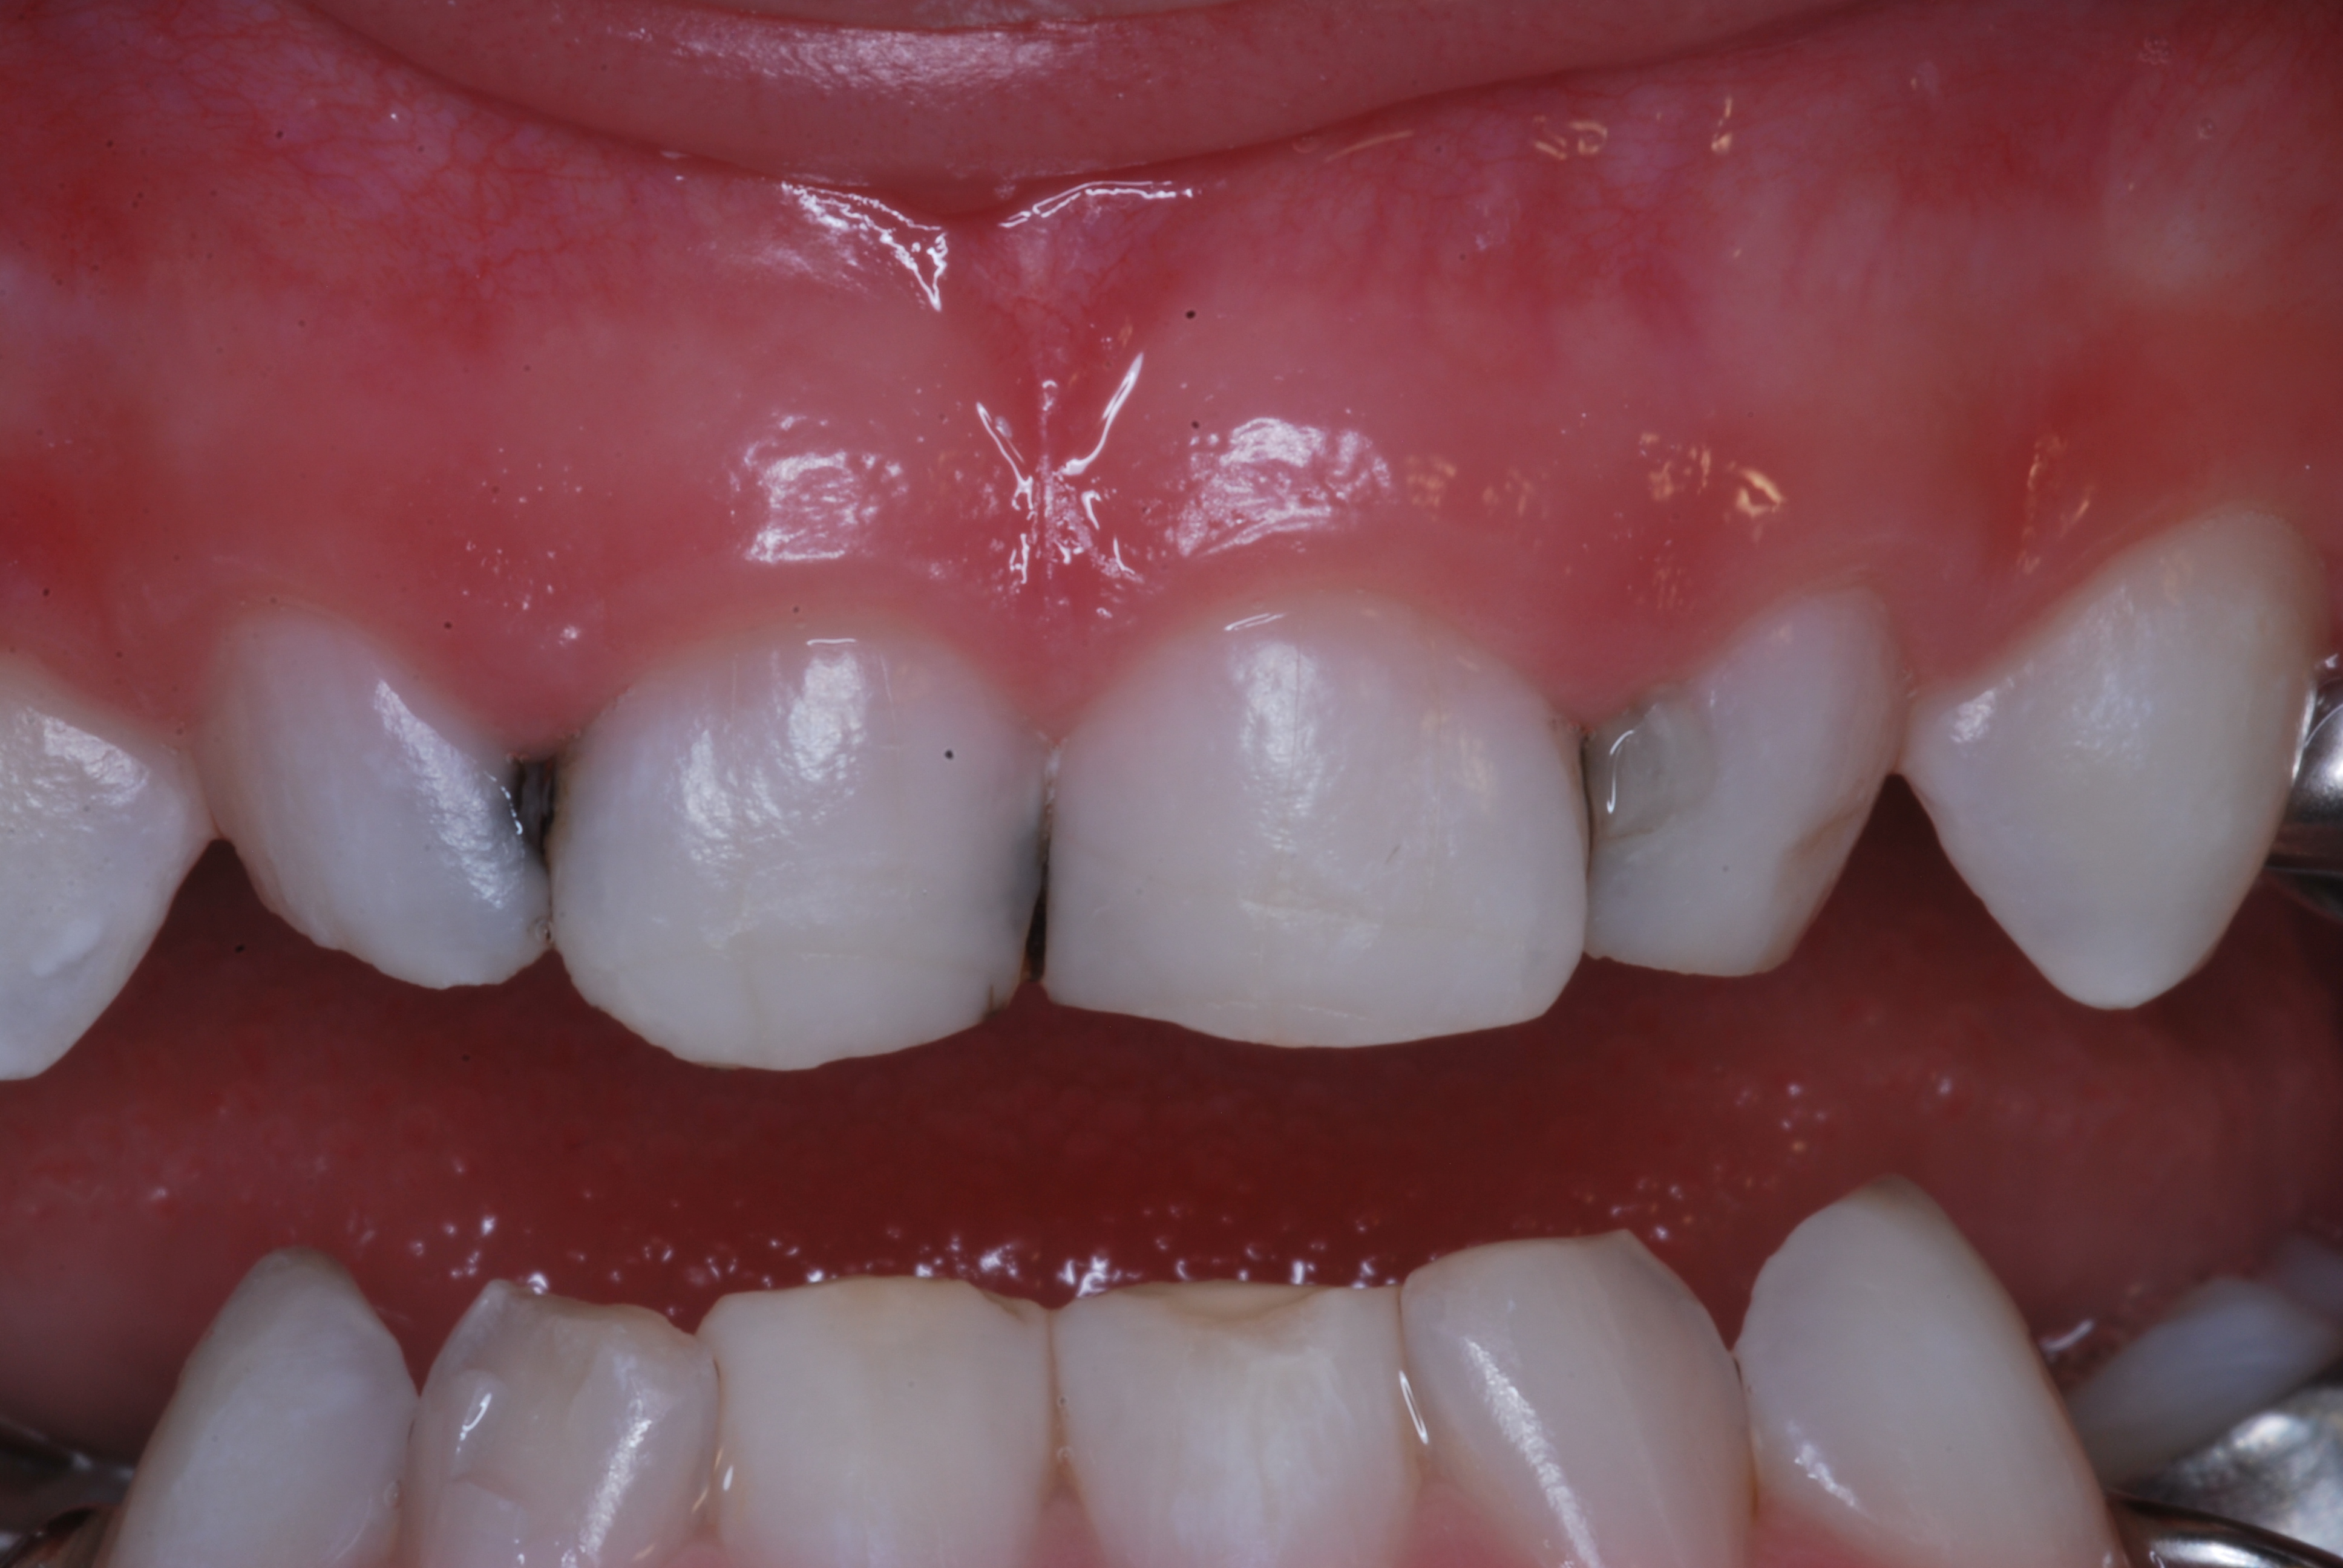

(2.) Lingual and facial maxillary views of 5-year-old patient, 1 year after caries attenuation with SDF. The parents were not concerned about the black staining.

Figure 2

(3.) Lingual and facial maxillary views of 5-year-old patient, 1 year after caries attenuation with SDF. The parents were not concerned about the black staining.

Figure 3